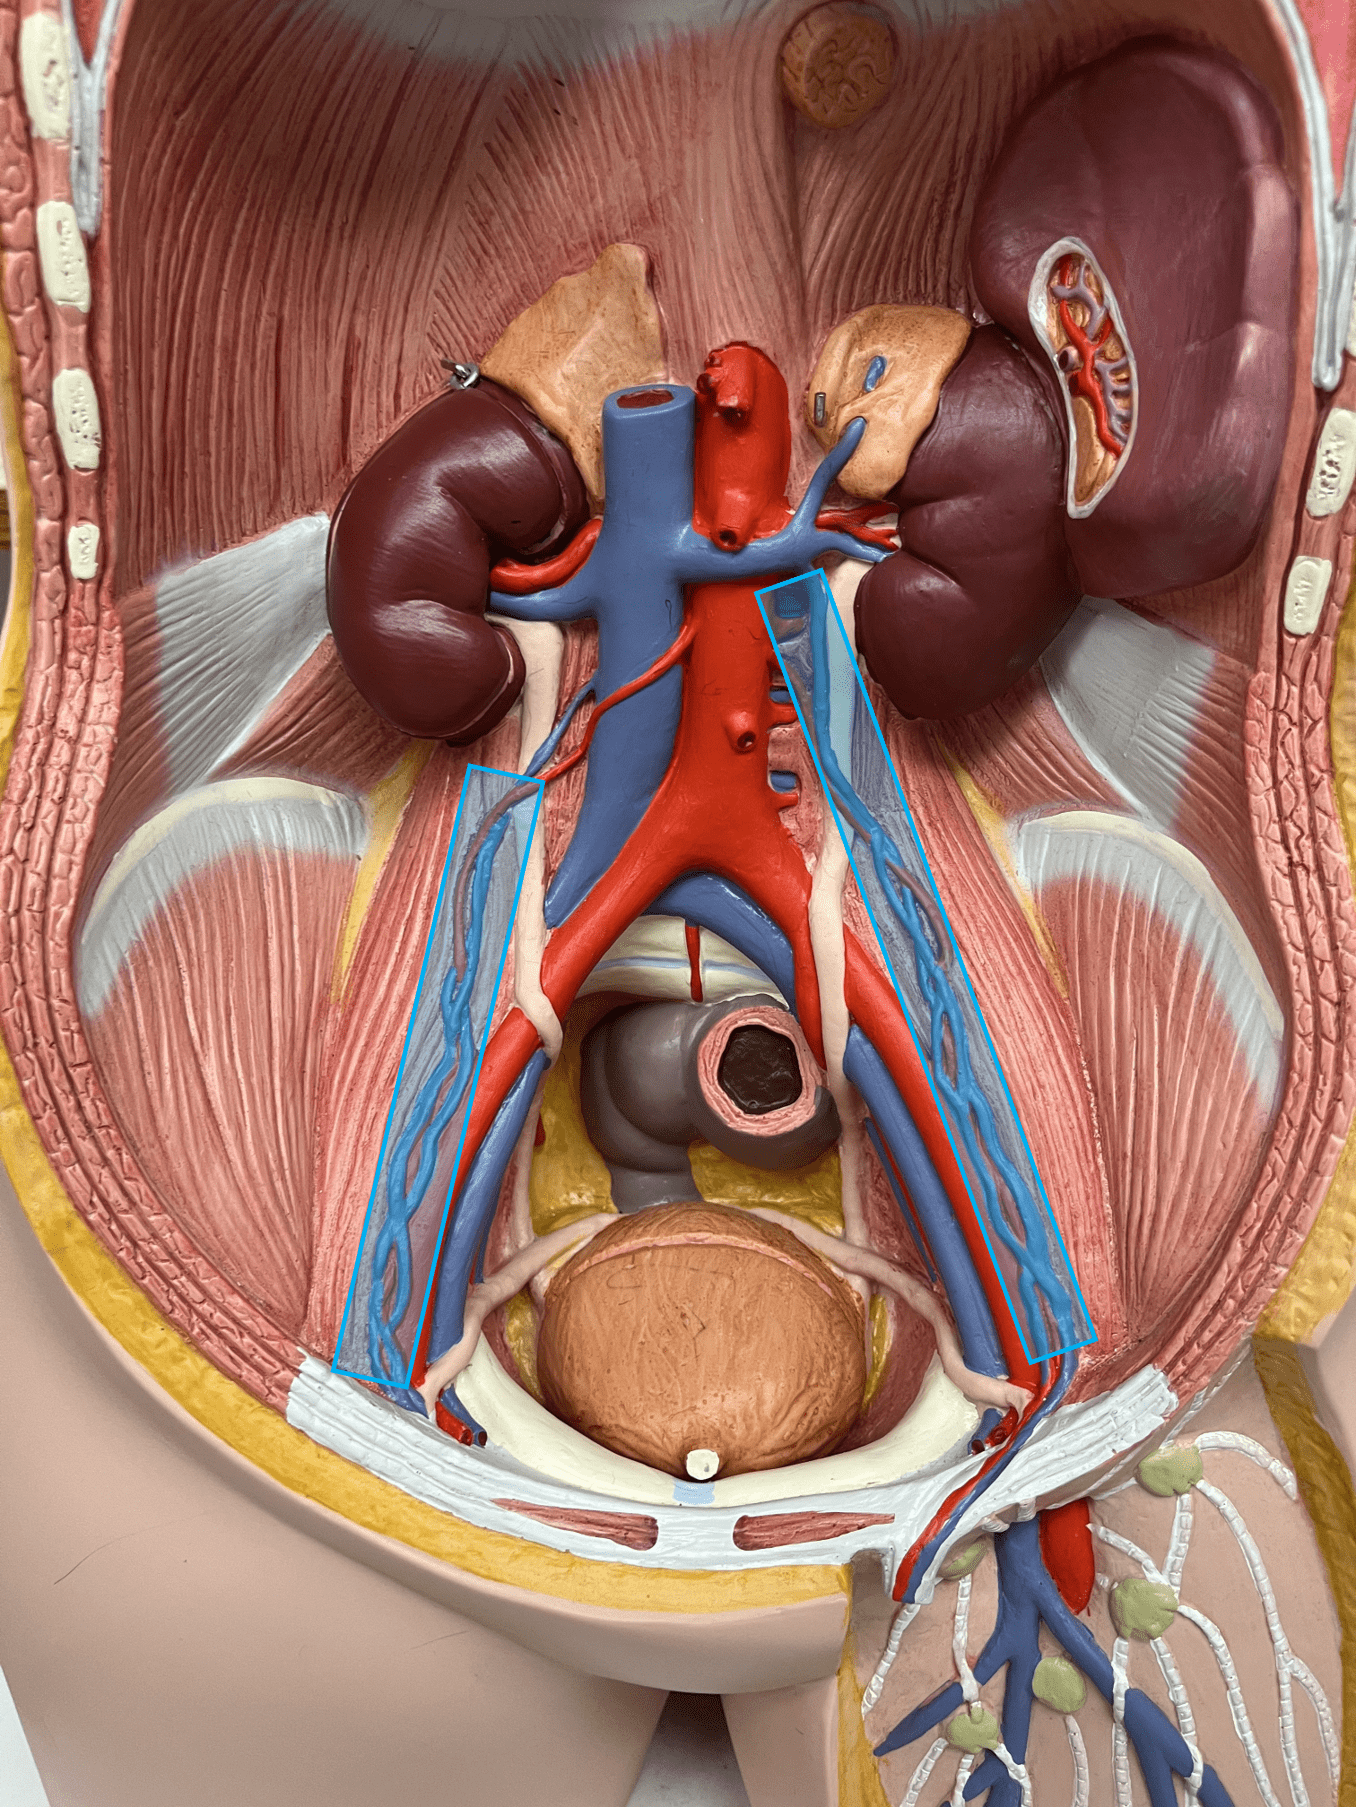

great saphenous vein

• A vein of the lower limb.

• Drains the medial lower leg and thigh.

• Empties into the femoral vein.

• Longest vein of the body.

• Drains the medial lower leg and thigh.

• Empties into the femoral vein.

• Longest vein of the body.

femoral vein

• A vein of the lower limb.

• Drains the deep thigh muscles.

• Empties into the external ilaic vein.

• Drains the deep thigh muscles.

• Empties into the external ilaic vein.

external iliac vein

• A vein of the lower limb.

• Drains all of the lower limb veins.

• Empties into the common iliac vein.

• Drains all of the lower limb veins.

• Empties into the common iliac vein.